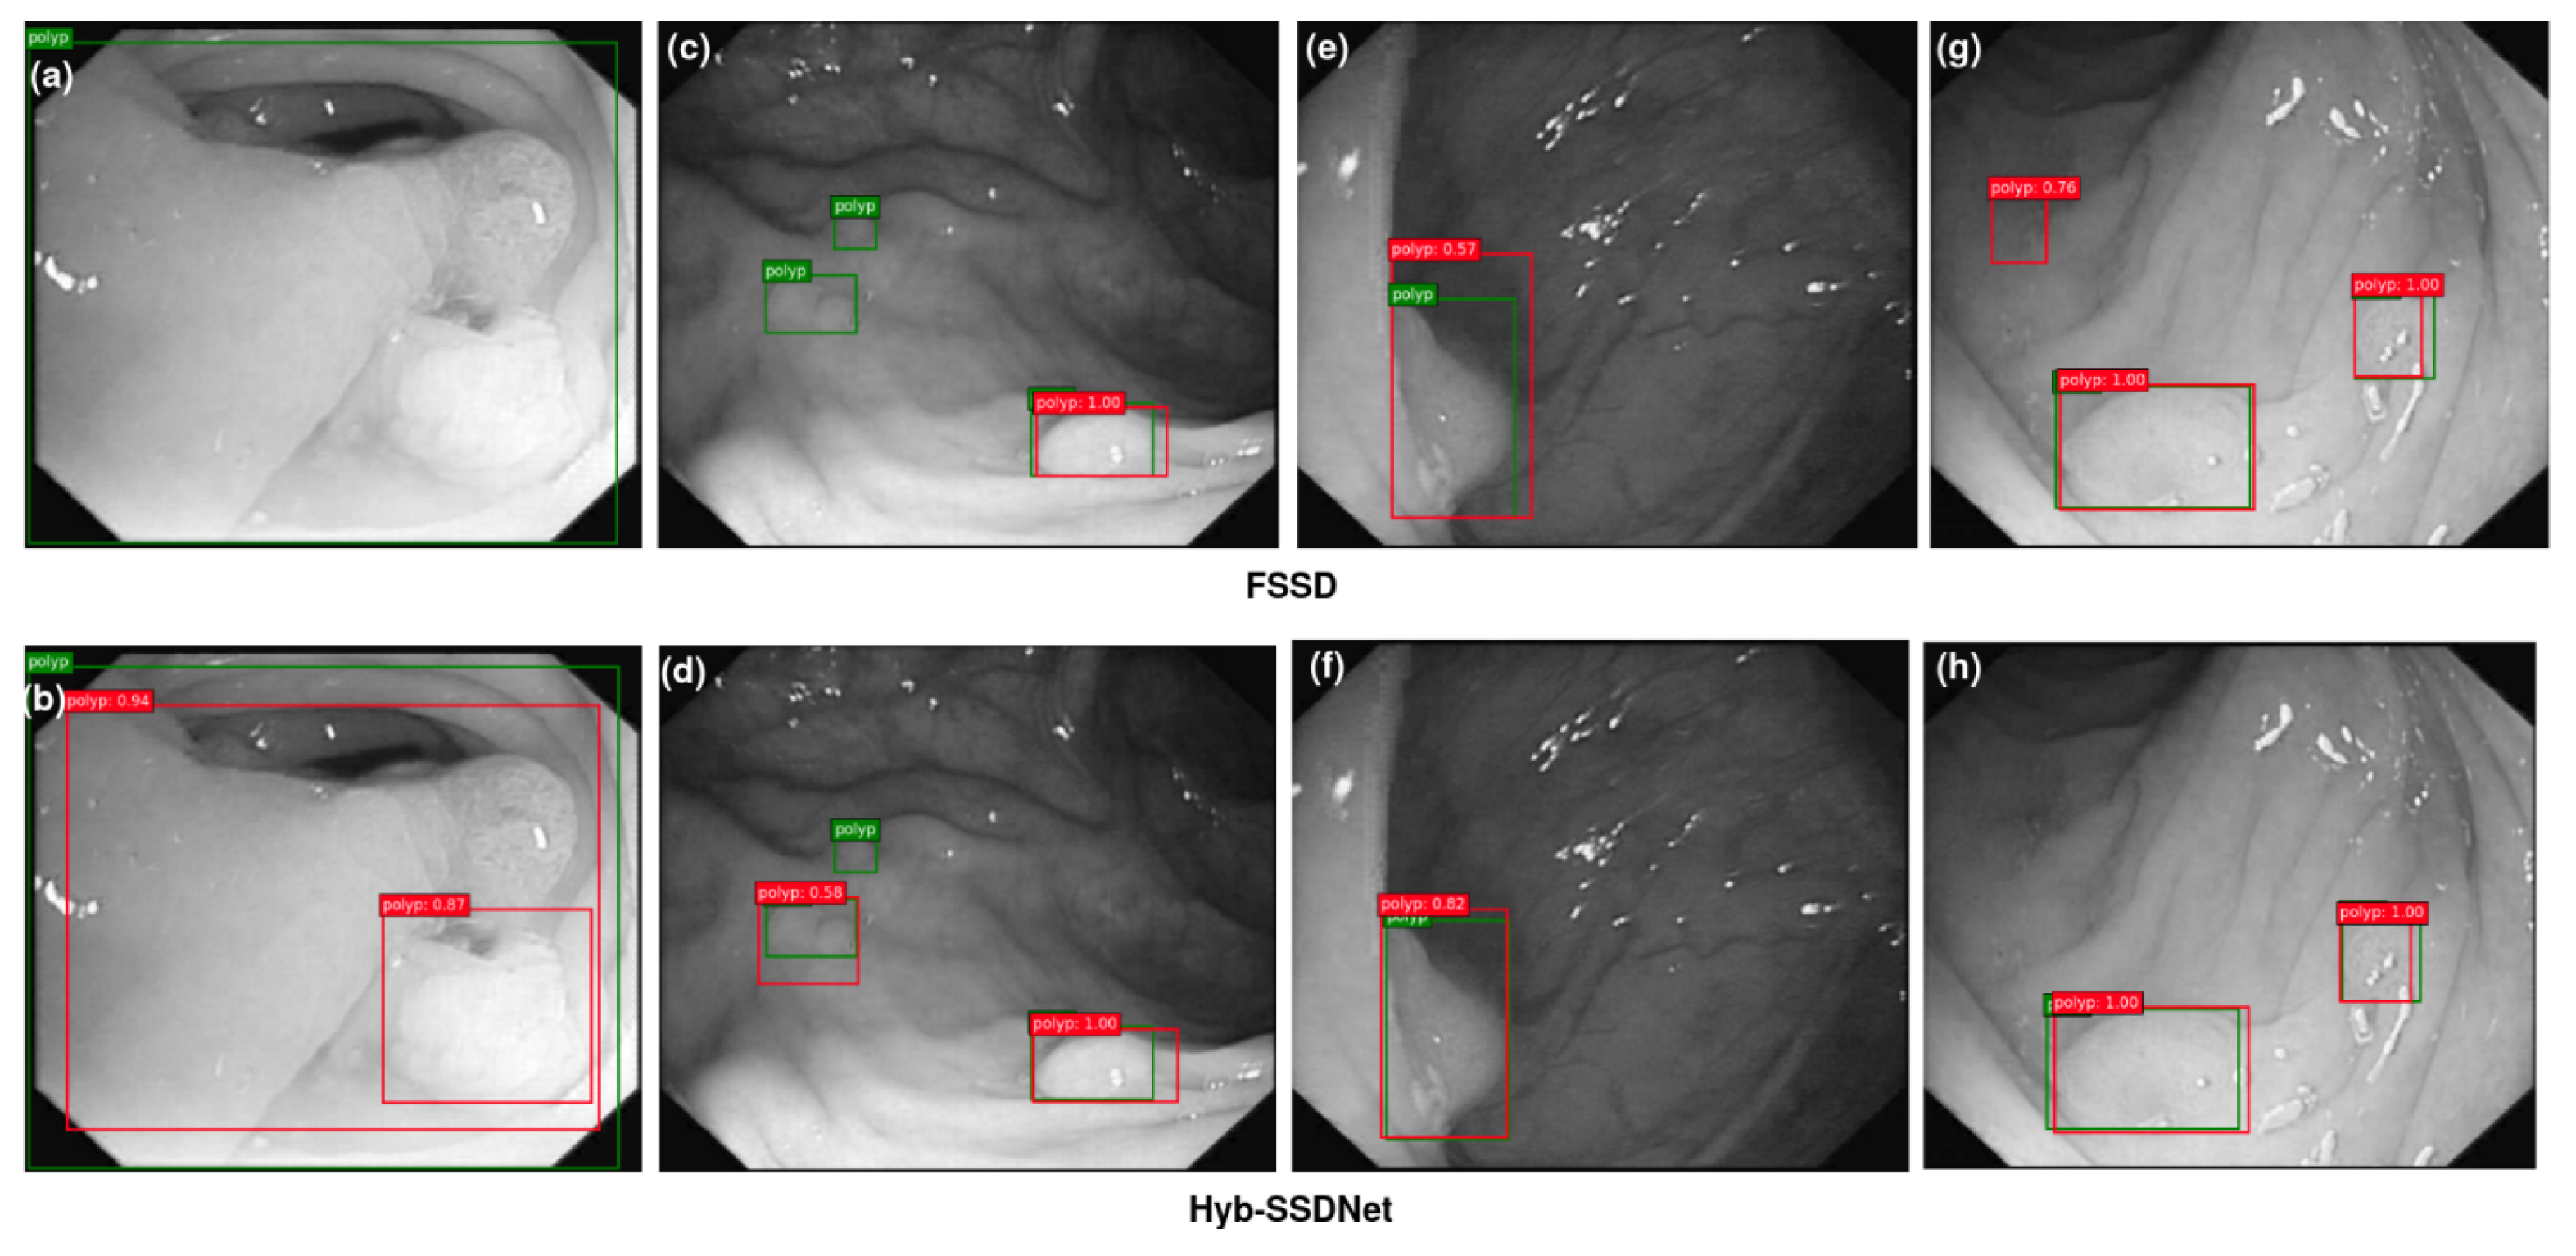

4.4.3. Visualization of Detection Results